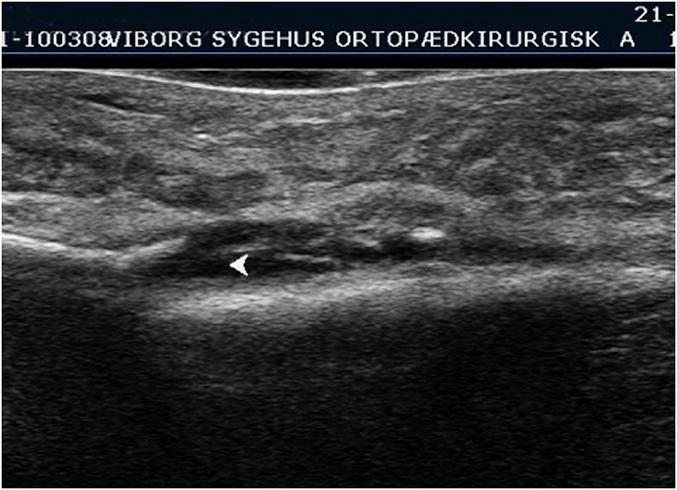

This prospective comparative study involved 91 patients (age, ≥18 years) who had been referred by general practitioners for a conventional radiographic examination of a suspected extremity fracture. No additional clinical examination was performed. Ultrasound examination was consistently carried out prior to conventional radiographic examination, which was regarded as the gold standard. At the end of the study, the positive scans were confirmed by a specialist who was highly skilled in ultrasonography.

The prevalence of fractures in the study population was 27%. Ultrasonography had a sensitivity of 92%, a specificity of 94%, a positive predictive value of 85%, a negative predictive value of 97%, a positive likelihood ratio of 15.33, and a negative likelihood ratio of 0.085. There seemed to be no association between the anomalous results and patient age or the specific anatomical region of the fracture.

The present study indicates that ultrasonography, when performed and interpreted by experienced ultrasonographers, has high accuracy for the diagnosis of a suspected extremity fracture. No systematic differences were found between the results of radiography and ultrasonography, and ultrasonography showed a high sensitivity and specificity.